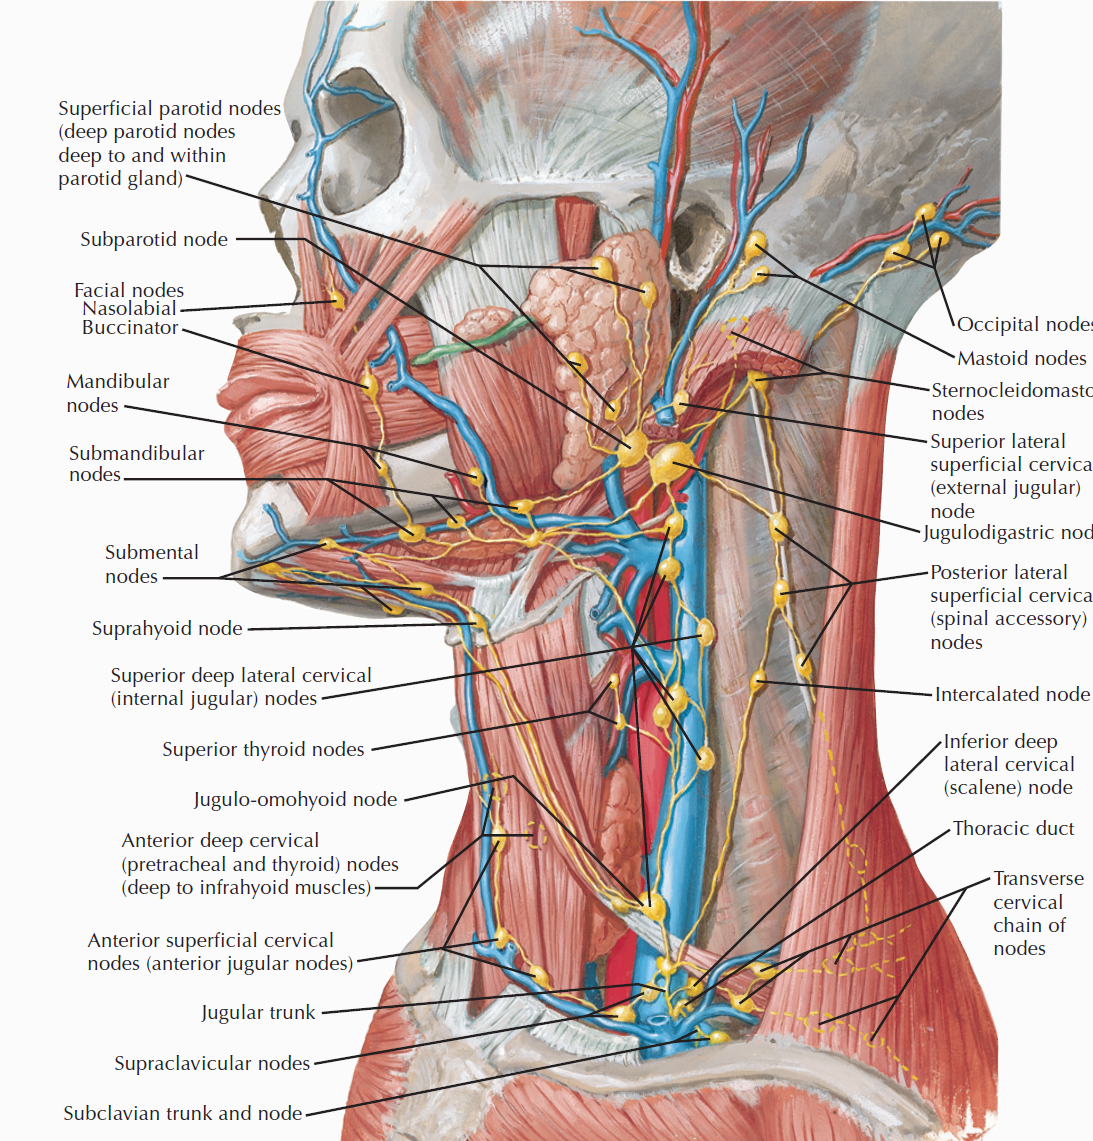

Lymphatic system

總圖

Nodes

Groups

- Level I

- the submental group (Ia), and the

submandibular group (Ib). - Level II

- the upper jugular lymph nodes

- level IIa – CN XI 前

- level IIb – CN XI 後

- Level III

- the middle jugular lymph nodes

- Level IV

- the lower jugular lymph nodes

- Level V

- all lymph nodes contained within the posterior triangle

- Level VI

- lymph nodes of the anterior (central) neck compartment

Tip

清除 I, II, III

Nasal cavity

Oral cavity

Tongue

Tonsil

Face

- Maxillary

- Buccinator

- Supramadibular

Larynx

用vocal fold 分,上,下分別到SDC, IDC

Thyroid

跟著Sup./ Inf. thyroid a.走,分別到SDC, IDC

Nose